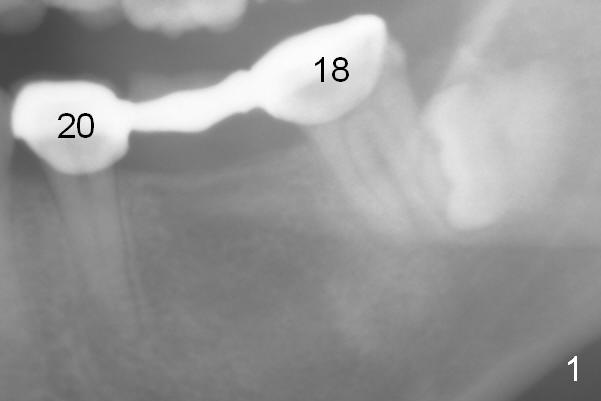

A 35-year-old lady (YL) has periodic nocturnal pain of the lower left quadrant. There is open buccal margin at the abutment of #18 (Fig.1 (from panoramus)). When the pontic and the retainer are removed (Fig.2), there is a large buccal subgingival carious lesion at the tooth #18. The latter has 2 roots, although close to each other. If the extraction turns out to be difficult, section the tooth (Fig.3 red line (no antibiotic)). To avoid contacting the tooth #17, place an implant at the mesial socket of #18 (Fig.5,7). Although it appears that the tooth #20 has no periapical radiolucency (Fig.6,7), the crown will be removed for diagnosis. A 3-unit provisional will be fabricated after an implant is placed at #19 (Fig.7,8) in the same appointment.